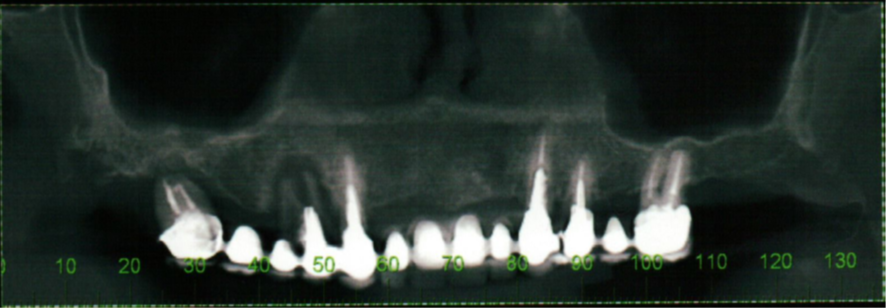

Paciente Leucoderma, de 50 anos, apresentava falência dos elementos superiores.

Foram planejados quatro implantes com distribuição biomecânica, segundo o polígono de Roy, de acordo com as radiografias transoperatórias abaixo.